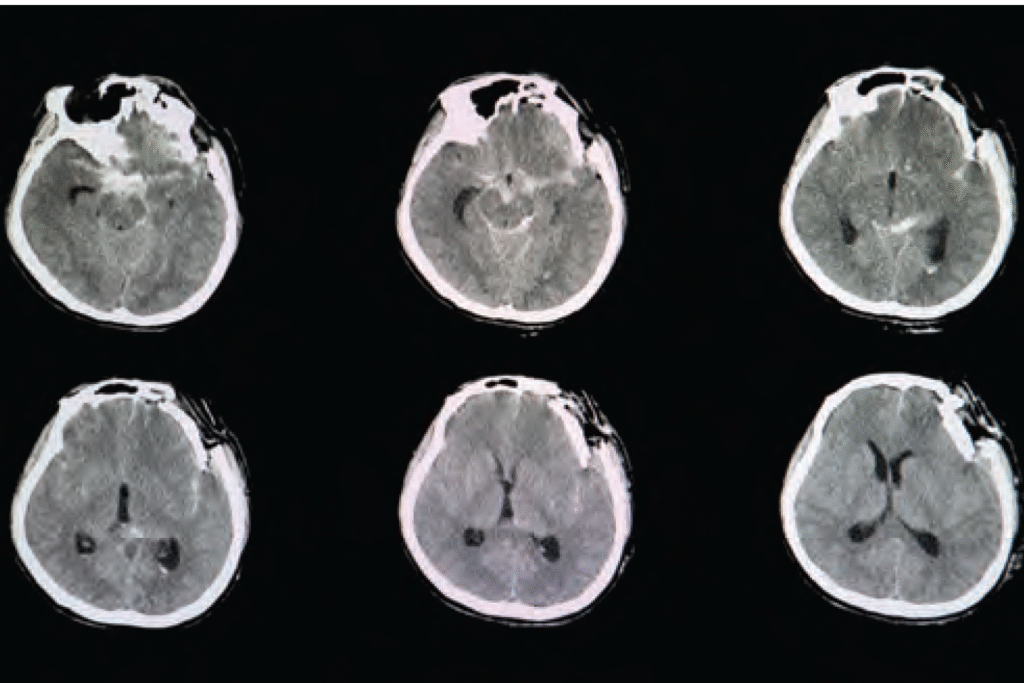

CT brain scan image of a patient with severe skull depression fracture at left frontal parietal area with left zygomatic arch and both maxillary sinuses fractures with small subarachnoidal hemorrhage.